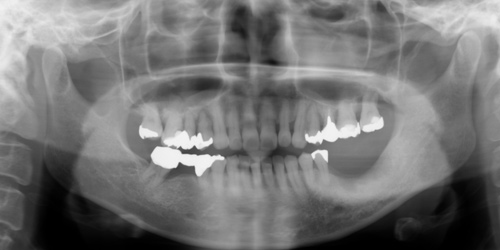

50代 女性

主訴 歯がグラグラしてかめない

治療内容 歯周治療 再生療法 歯肉移植

インプラント治療 サイナスリフト 垂直的骨造成

治療前